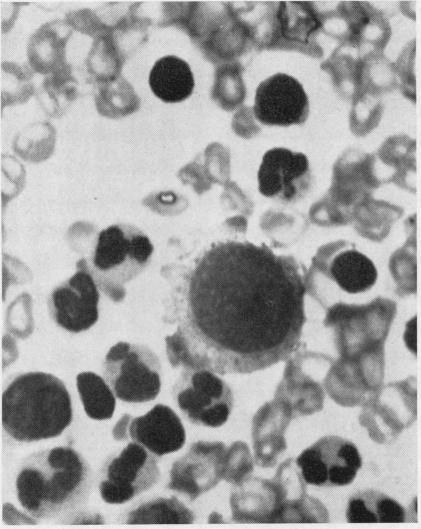

White-cell concentrates were made by a dextran sedimentation technique from the blood of 140 cases of malignant disease and 60 controls. The slides were searched for tumour cells and for other unusual cells with which they might be confused. Several million white cells were scanned in the slides from each case. Acceptable tumour cells were identified in the blood of seven patients, none of whom survived for more than a few months. These cells are illustrated, as well as various other cell types which may have been confused with malignant cells in the past. It is concluded that the cytology of white cell concentrates should be further explored before statistics about the occurrence of circulating tumour cells are accepted.

采用葡聚糖沉降技术从140例恶性疾病患者及60例对照者的血液中制备白细胞浓缩物。在玻片上查找肿瘤细胞以及可能与之混淆的其他异常细胞。对每个病例的玻片扫描数百万个白细胞。在7名患者的血液中鉴定出了可接受的肿瘤细胞,其中无一例存活超过几个月。文中展示了这些细胞以及过去可能与恶性细胞混淆的各种其他细胞类型。得出的结论是,在接受关于循环肿瘤细胞发生率的统计数据之前,应进一步探索白细胞浓缩物的细胞学。